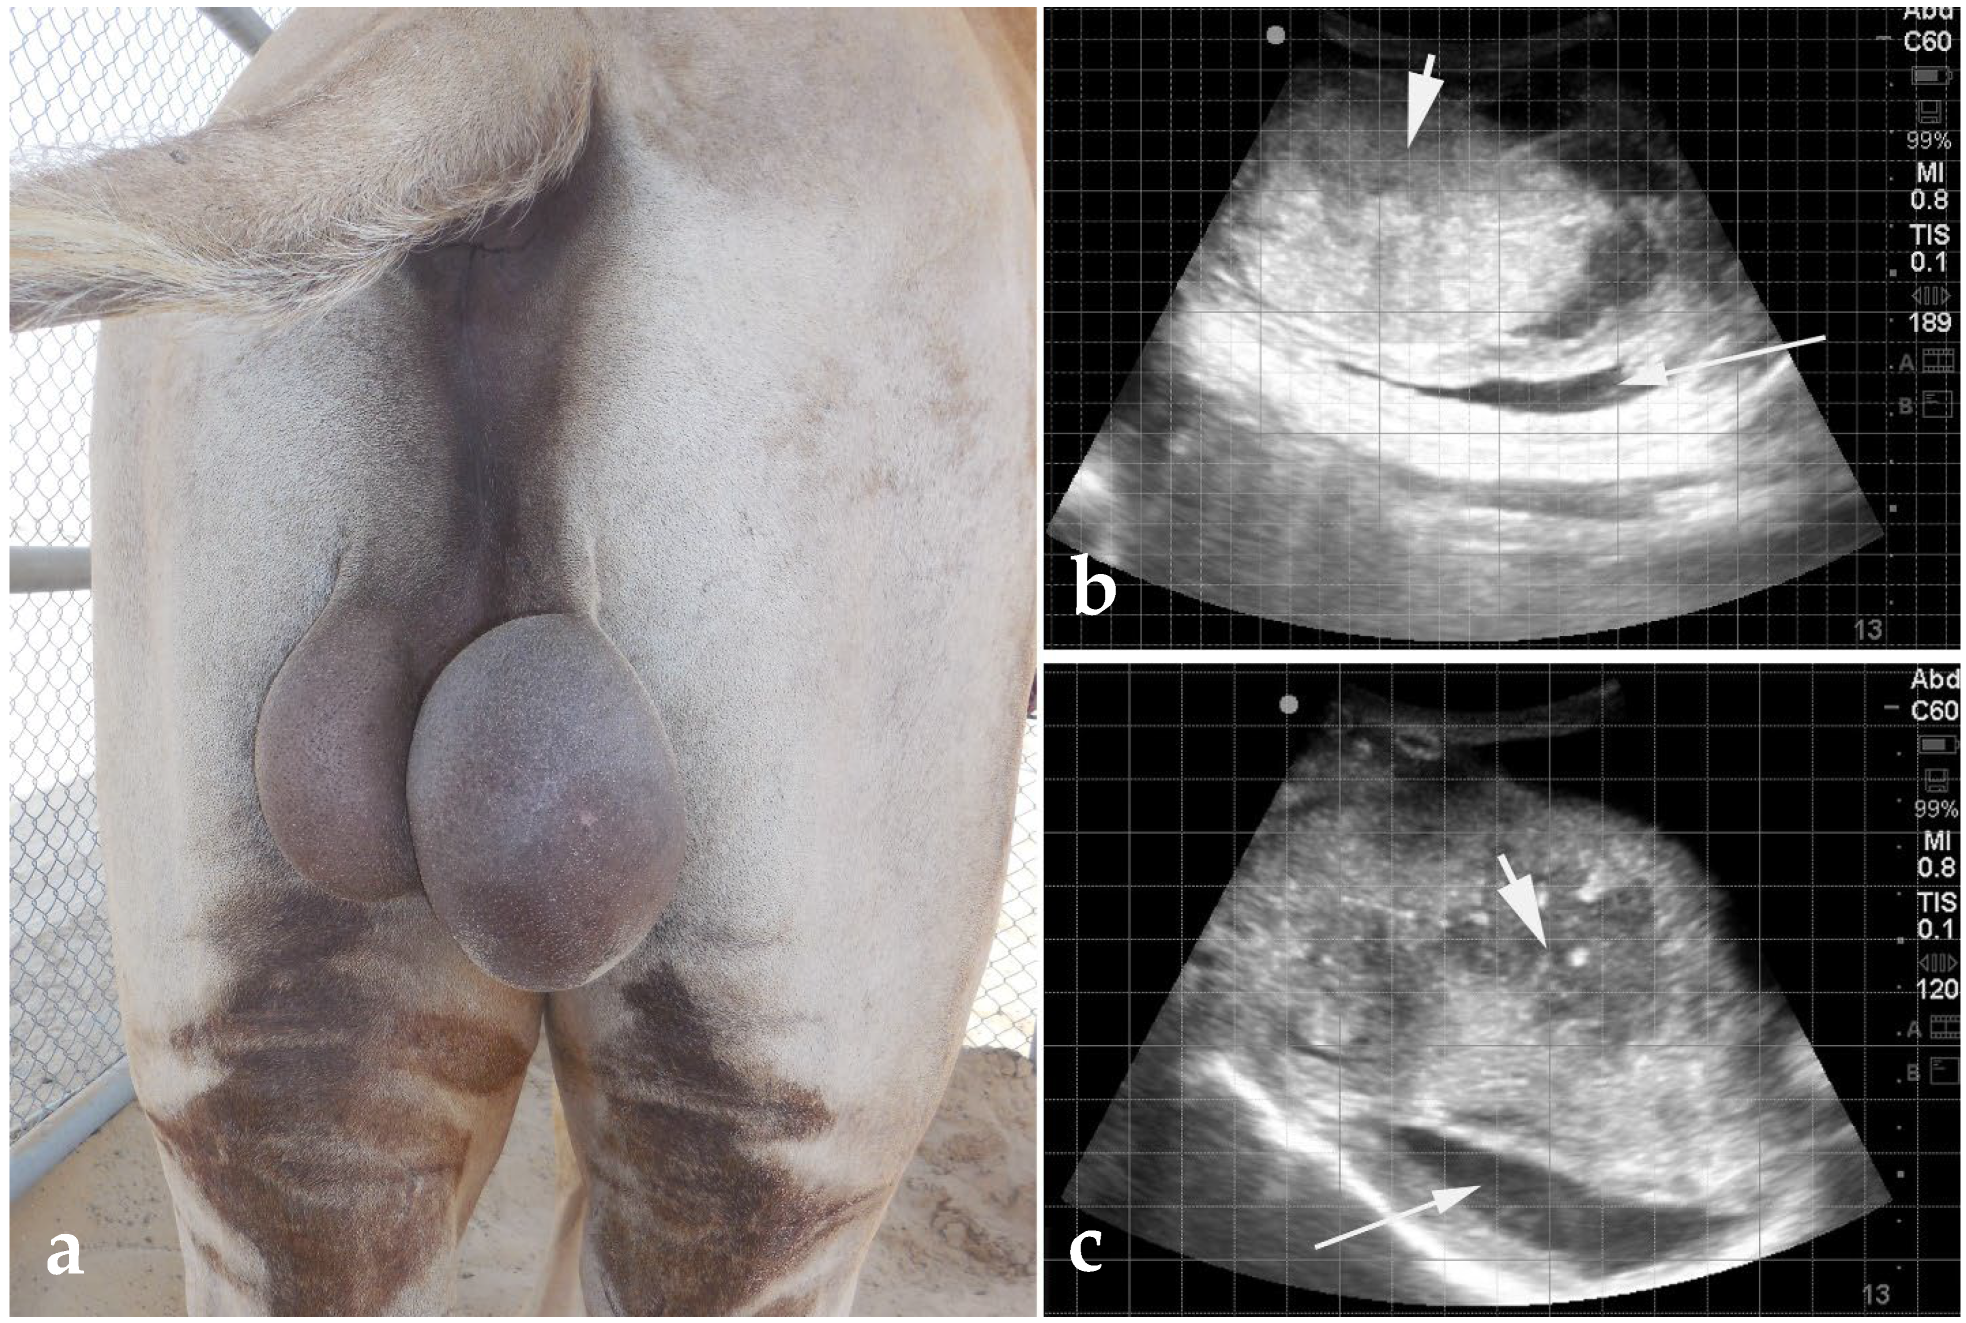

6.1. Scrotal Enlargement

- Tibary, A.; Pearson, L.K. Reproductive Emergencies in Camelids. Clin. Theriogenol. 2014, 6, 579–592. [Google Scholar] [CrossRef] [PubMed]

- Tibary, A.; Rodriguez, J.; Sandoval, S. Reproductive Emergencies in Camelids. Theriogenology 2008, 70, 515–534. [Google Scholar] [CrossRef]